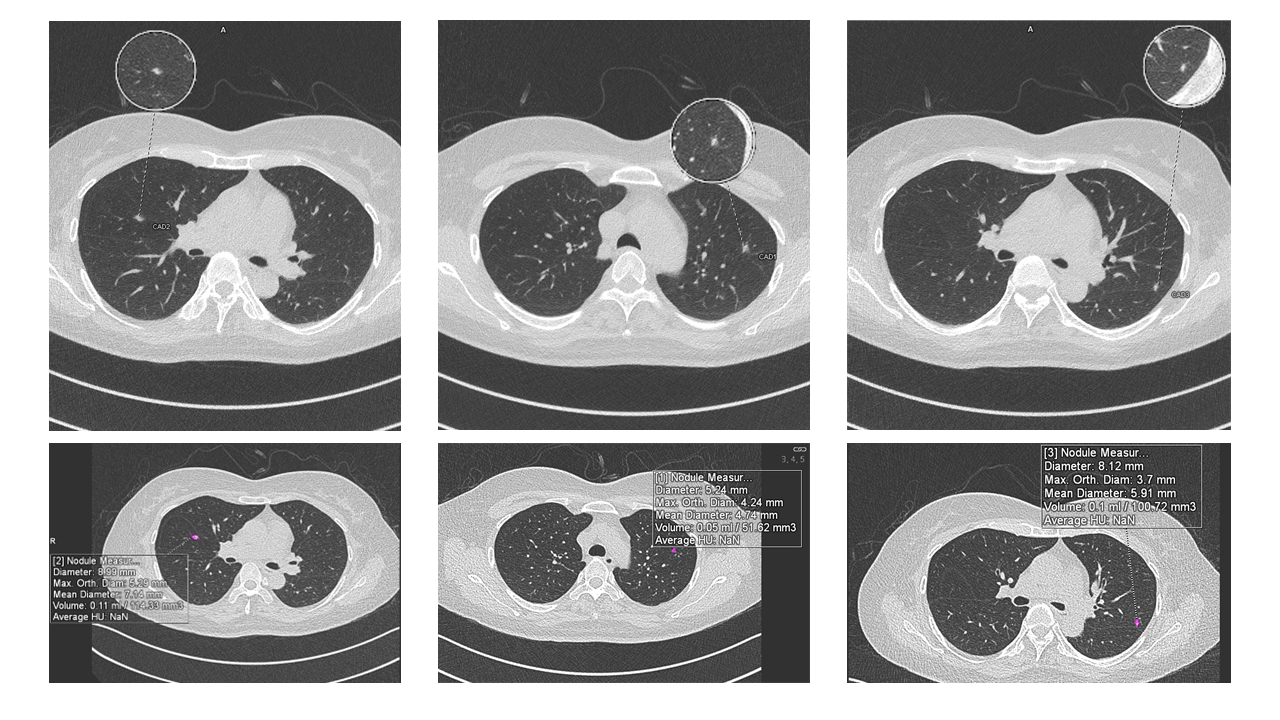

- Nodule detection and volumetry to support Low Dose CT (LDCT) screening

She shared multiple case examples including a post-lobectomy patient with suspicious nodules and a systemic sclerosis case with subtle Interstitial Lung Disease progression - highlighting how AI-powered volumetry and CT densitometry aided confident diagnosis and follow-up.

“LDCT gives us eyes, but workstations give us clarity ,” she said, pointing to how CAD tools reduce oversight and support longitudinal follow-up with reproducible quantification.